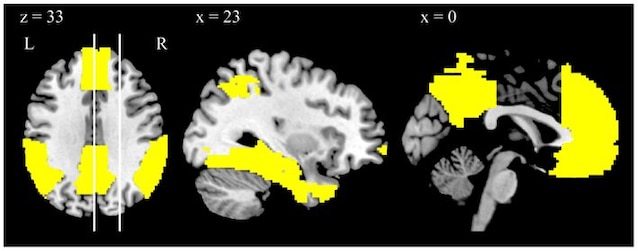

La tanker gå, oppfyller minner om fortidens følelser tilfeldig, reflekterer uten begrensninger i livet vårt. Alt dette avhenger av en nevralt nettverk i hjernen vår: den Standard modusnettverk (DMN), som inkluderer bakre cing, prefrontale og tidsmessige cortexes og preconeum. Når vi er en hvile Hjernen vår stopper ikke i det hele tatt. Tvert imot, det går inn i en fase med intens mental aktivitet, og utløser DMN som omhandler forskjellige viktige oppgaver: det får oss til å tenke på tidligere hendelser og forestille oss fremtidige situasjoner, oppfinner Mulige scenarierhjelper oss med å forstå hvem vi er og hvordan vi forholder oss til andre, og lar oss gjøre det Omfattende følelser.

Dets særegenhet er å være en enorm utbredt nettverkog takket være denne brede strukturen tillater det Integrering av informasjon mellom cerebrale områder veldig fjernt fra hverandre. I øyeblikkene når DMN er aktivert, lar vi rom for hjernen vår til å tisse og koble til fjerne tanker, slik at vi kan koble oss problemer og finn løsninger på en åpen og kreativ måte.